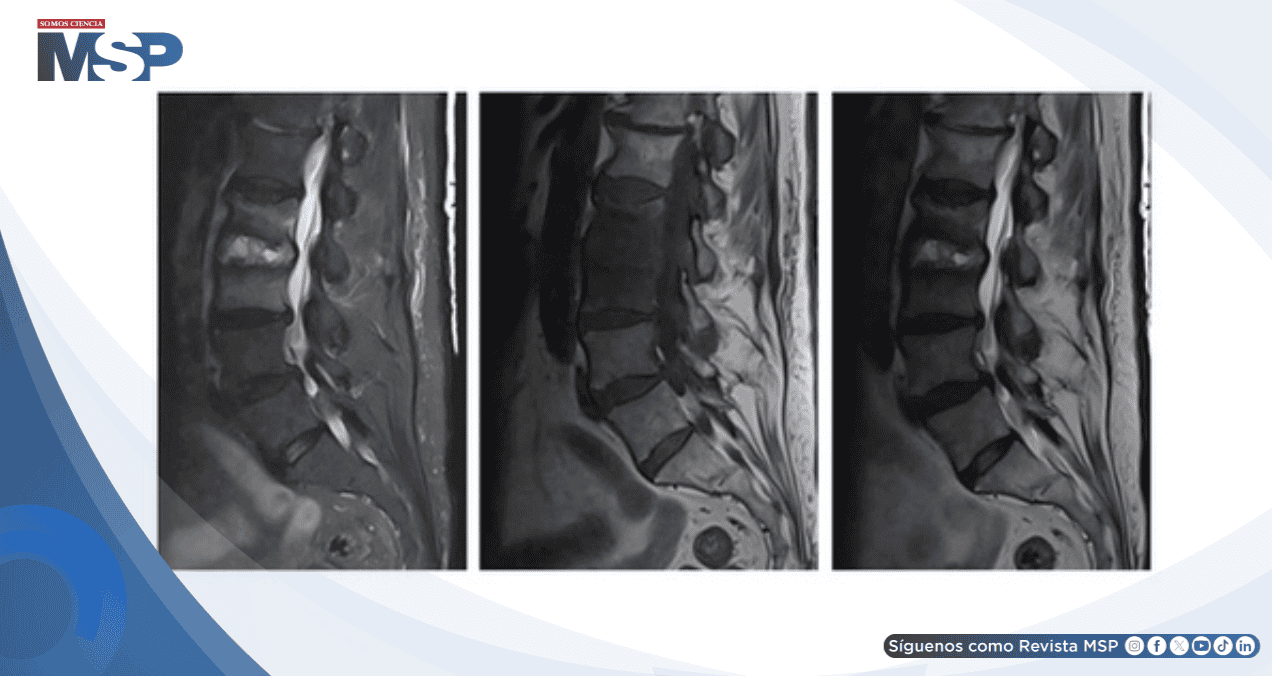

La resonancia magnética de columna lumbar reveló señal infiltrativa en T1 que involucraba los cuerpos vertebrales L2 y L3 con realce poscontraste asociado y líquido en el espacio discal L2-L3, hallazgos compatibles con discitis y osteomielitis.